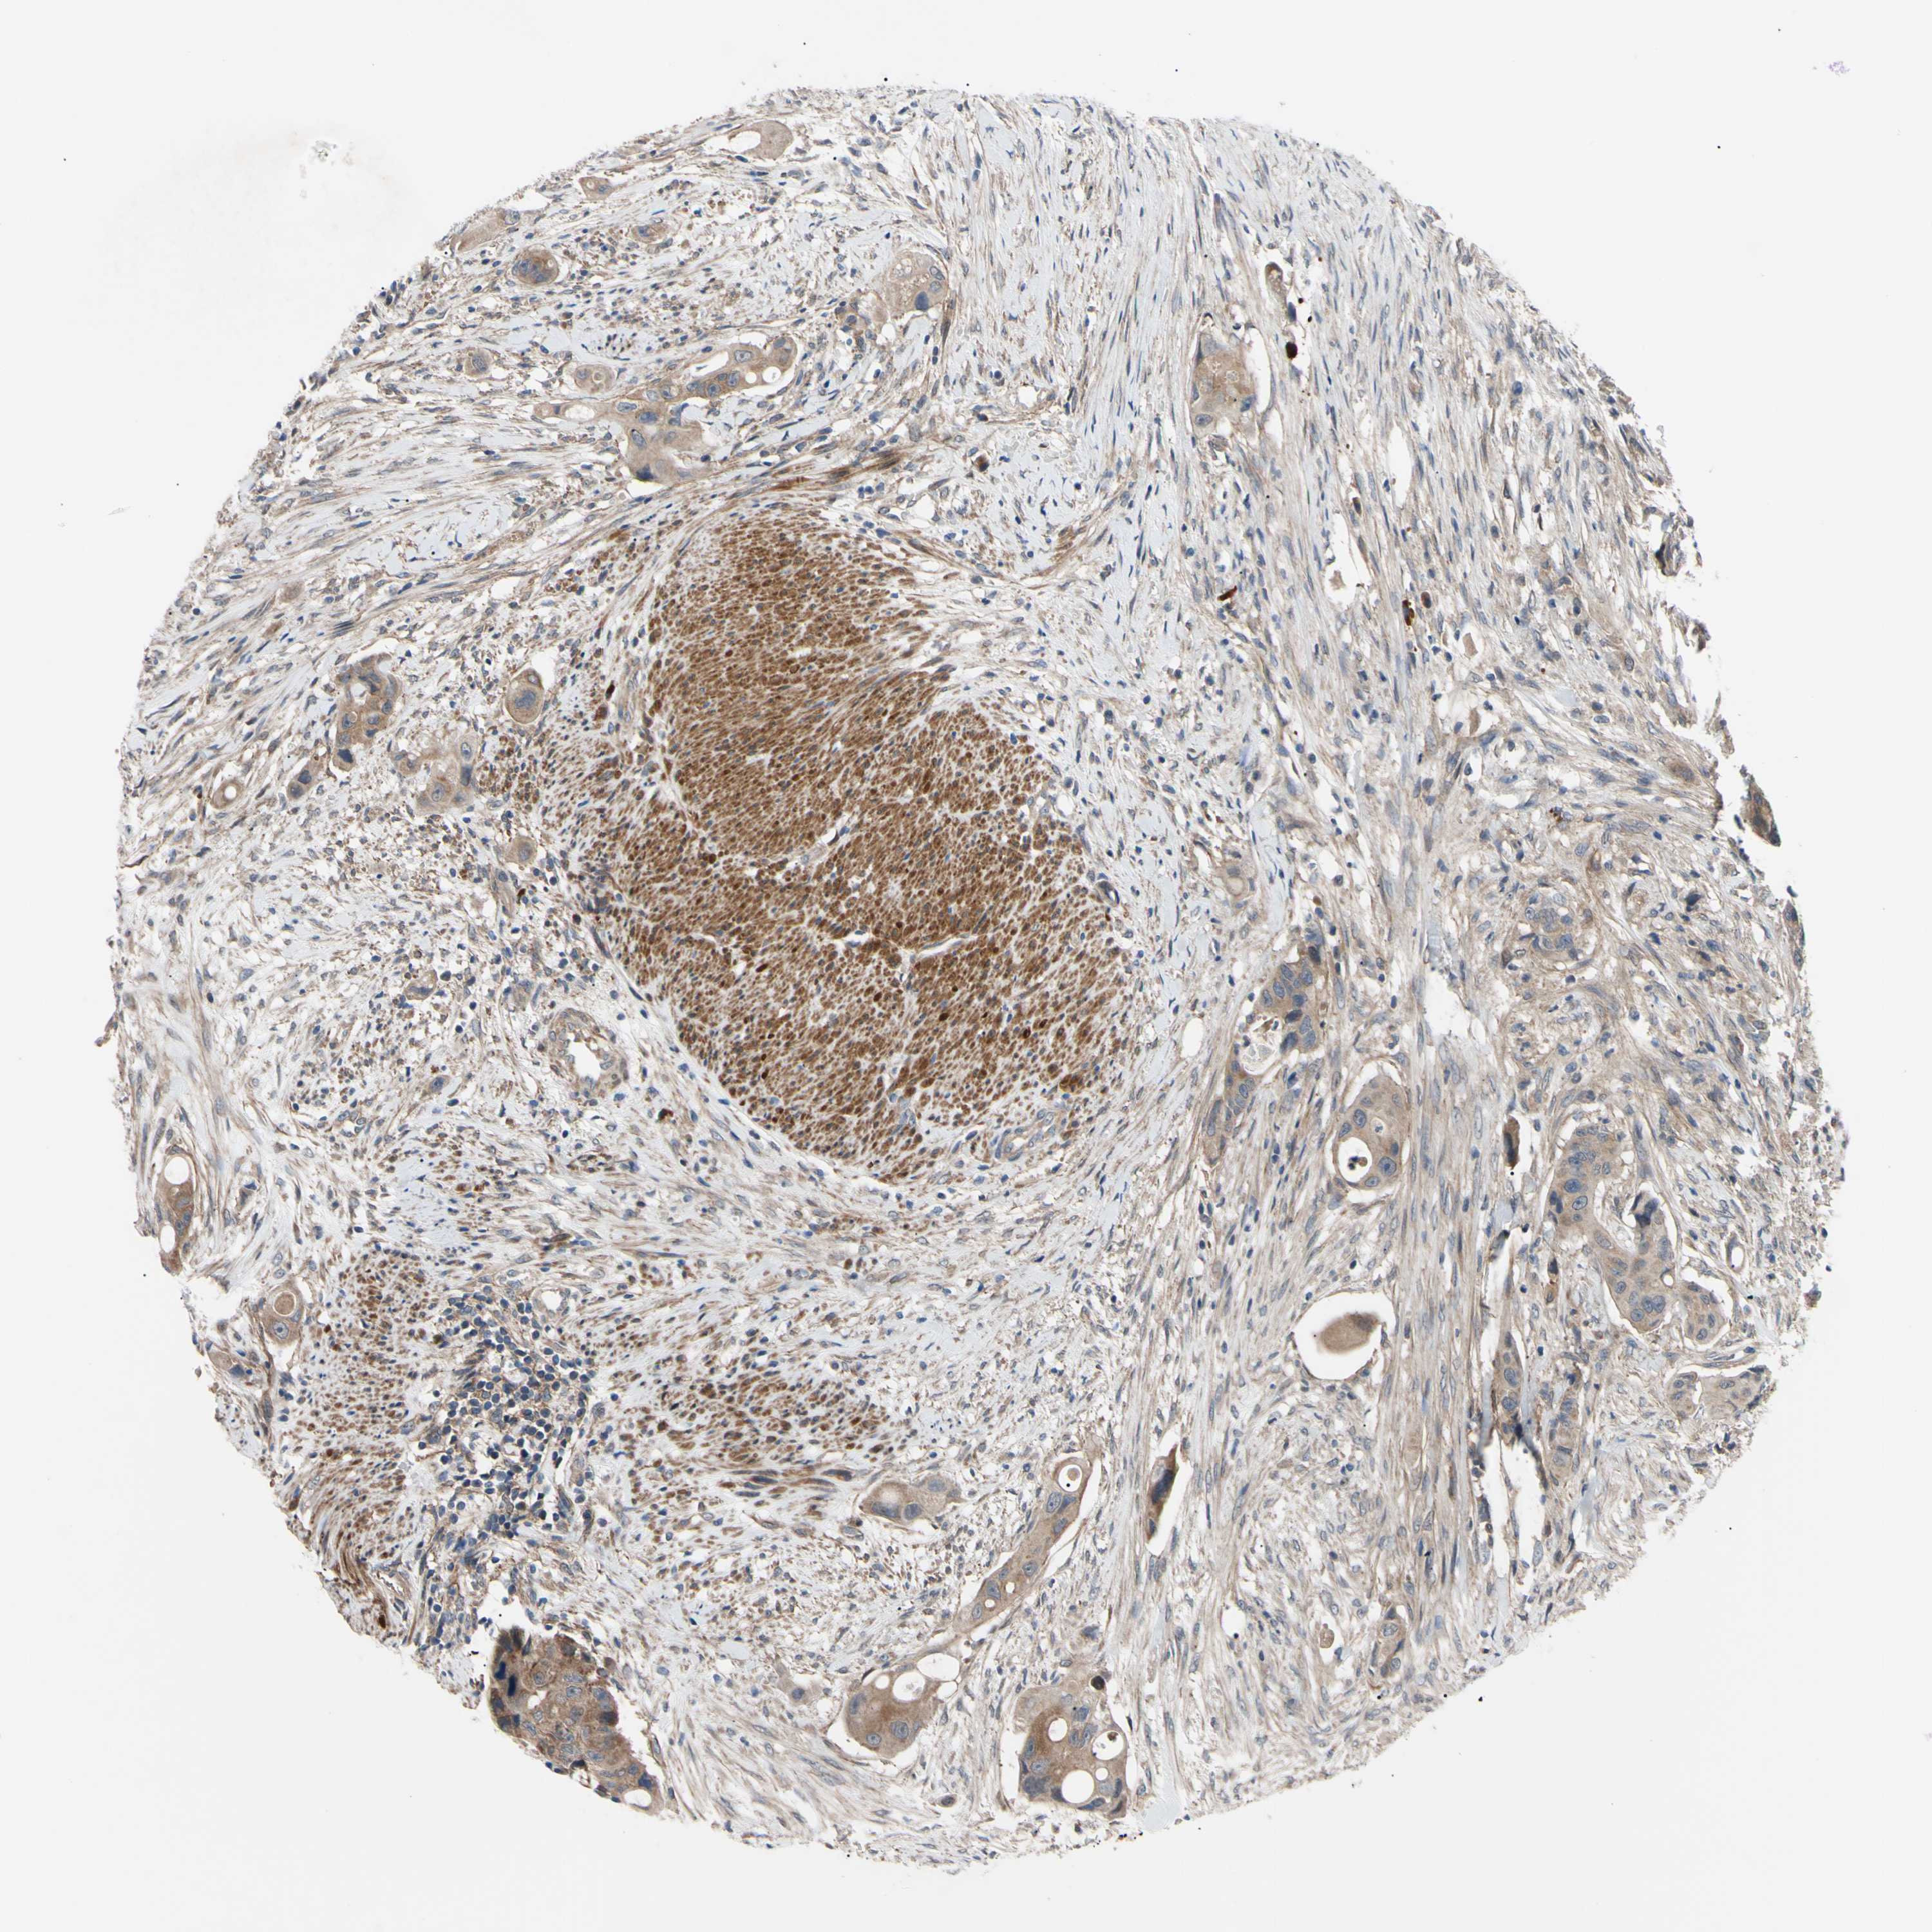

Colorectal cancer

Human cancer

Colon adenocarcinoma

Rectum adenocarcinoma